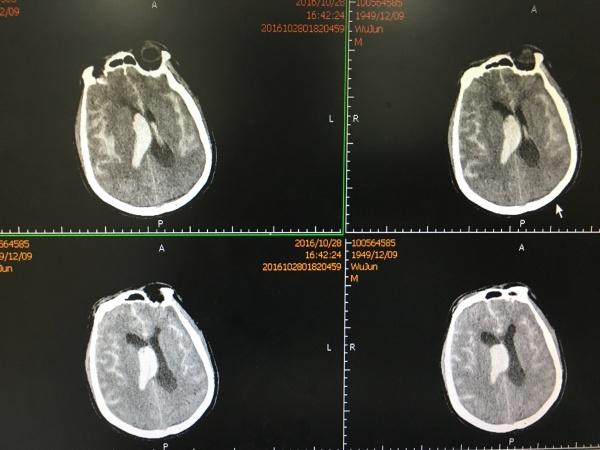

又是一个不珍惜自己的病例! 患者老年男性,半年前因突发头痛于外院就诊,行头颅CTA检查示右侧 Middle celebral artery M2 动脉瘤,因出血量少,患者意识清晰,故未听从医生的建议手术治疗,而是待出血吸收后返家,而且照常通宵打牌、吸烟、喝酒。 终于,上月底,老天给他记了大过: 患者在亲戚家玩麻将时突发头痛、呕吐伴肢体乏力,急送我院,行“头颅CT“示广泛SAH伴右侧侧裂内血肿,患者逐渐出现嗜睡、大小便失禁、呼之不应,急转至我院急诊,行头颅CTA检查示右侧MCA M2段动脉瘤,此时,患者已深昏迷,GCS:4分。

片中示巨大脑内血肿,而且出血破入脑室,右侧侧脑室铸型。

我们急诊在全麻下行开颅血肿清除+动脉瘤夹闭+颅内压监护探头植入术,术后复查头颅CT如下: